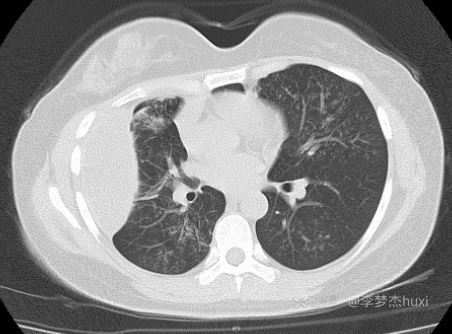

主诉:1月前体检发现右侧包裹性胸腔积液,肺部无异常,未进一步诊治。一月后复查除了包裹性胸腔积液外,肺内增加了多发结节影。无发热,无呼吸道症状。